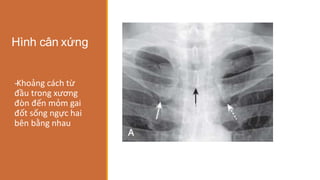

Hình cân xứng

‐Khoảng cách từ

đầu trong xương

đòn đến mỏm gai

đốt sống ngực hai

bên bằng nhau